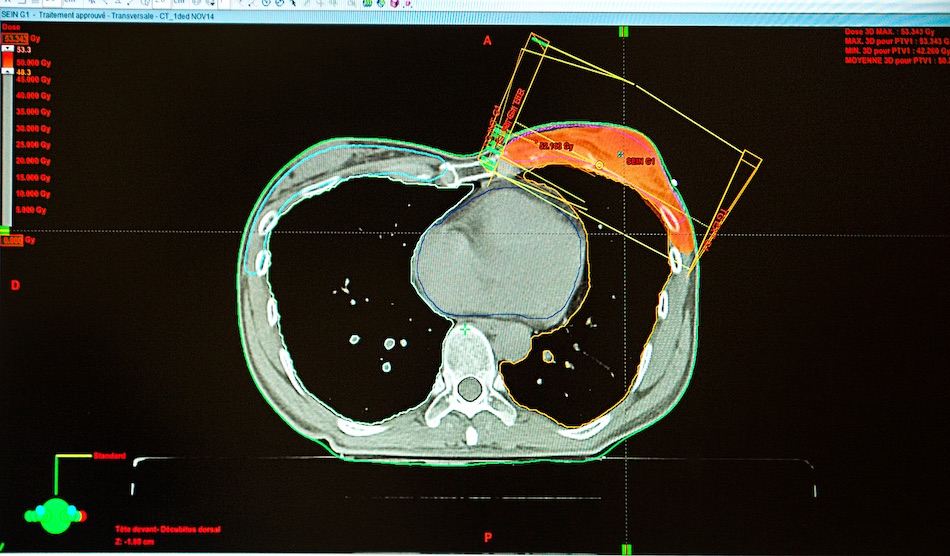

Radiothérapie : oui dans le cancer précoce, mais non à l’irradiation de paroi

Deux présentations au San Antonio Breast Cancer Symposium (SABCS) ont abordé des aspects de la radiothérapie dans le cancer du sein précoce ou intermédiaire.